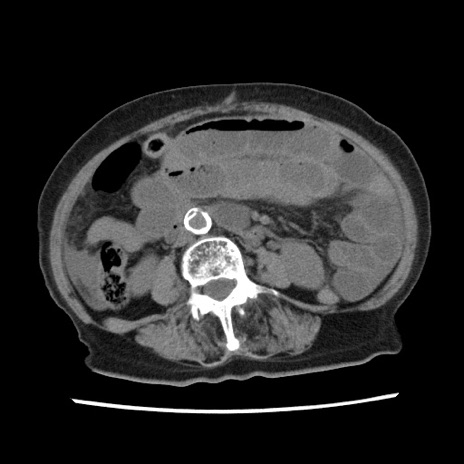

【症例】80歳代女性

【主訴】腹痛

【現病歴】8時間前から腹痛あり来院。

【既往歴】糖尿病、脂質異常症、子宮体癌にて子宮全摘術

【身体所見】意識清明・会話良好だが腹痛で苦悶様、全腹部にわたって反跳痛と圧痛あり

【データ】WBC 13600、CRP 0.14、LDH 224、CK 90